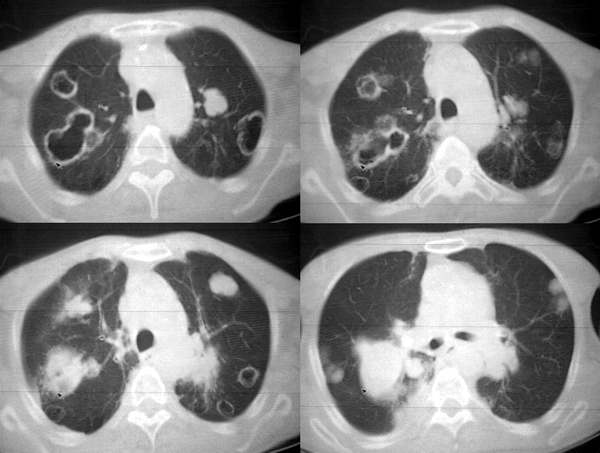

男62肺癌治疗后复查

具体治疗措施不清楚,治疗前空洞很少,请讨论空洞的性质

双肺内及胸壁旁见有多发软组织实性阴影和空洞,实性病变多见有脐凹切迹,贴近胸膜的见有胸膜凹陷征;空洞的壁多为厚薄不均,形态不规则,纵隔内见有较多肿大淋巴结,诊断为双肺内转移性病变。

双肺内及胸壁旁见有多发软组织实性阴影和空洞,实性病变多见有脐凹切迹,贴近胸膜的见有胸膜凹陷征;空洞的壁多为厚薄不均,形态不规则,纵隔内见有较多肿大淋巴结,诊断为双肺内转移性病变。[气囊或孔洞实为腺癌缘肺泡壁生长所致]

肺癌双肺内多发空洞转移,原发灶多为腺癌,恶性程度较高.

3.3 cpm的ct特征

cpm灶多为圆形或类圆形、无分叶和毛刺,说明除空洞外cpm 基本保留了转移瘤的形态特点。本组中单个病例出现cpm灶1 16枚,多发与单发者大致相等,说明cpm瘤灶的数目变化大。全部病例的cpm灶均是与肺内多发实性瘤灶共存,而且后者往往远多于前者。另外,当病情好转或恶化时,cpm灶与实性瘤灶同时缩小或增大,说明两者呈同步变化。笔者认为这两点是cpm 最恒定的ct特点。•

单个cpm灶的空洞形态具有多样性,壁可薄可厚,厚度可均匀可不均匀,瘤灶大小变化也大。但总的说来,cpm 的洞壁较薄,4mm以下者最多(53%),其次为4—15mm者(34%),而15mm以上者却较少。另外洞壁厚度均匀者也较多(47%)。笔者认为这些与壁薄而均匀的囊样及小环形空洞较多有关。一般认为壁薄而均匀者多为良性空洞,而癌性空洞的壁多较厚或厚薄不均。woodring等-8 j认为洞壁厚度4mm以下者92%为良性,15mm 以上者95%为恶性,15mm者良恶性各半。蒋瑾等-9 j发现83% 的原发空洞型肺癌的壁厚度超过15mm。以上说明cpm的空洞形态不同于肺良性空洞及原发癌性空洞,具有其独特性。本组40%(16/40)的病例中同时存在多种空洞,说明cpm病例具有空洞类型的混合性。同样的洞腔变化既可见于病情好转时,也可见于病情恶化时,特别是同一种病例可同时出现两种相反的洞腔变化,说明洞腔变化具有非恒定性。

右肺门软组织块影,右主支气管及中间段支气管管壁明显增厚,两肺内多发结节及大小不等的类圆形薄壁空洞,纵隔内多发肿大的淋巴结;

考虑:1.右中央型肺癌伴两肺广泛性转移及纵隔转移。

2.多发性空洞需和霉菌性空洞鉴别。